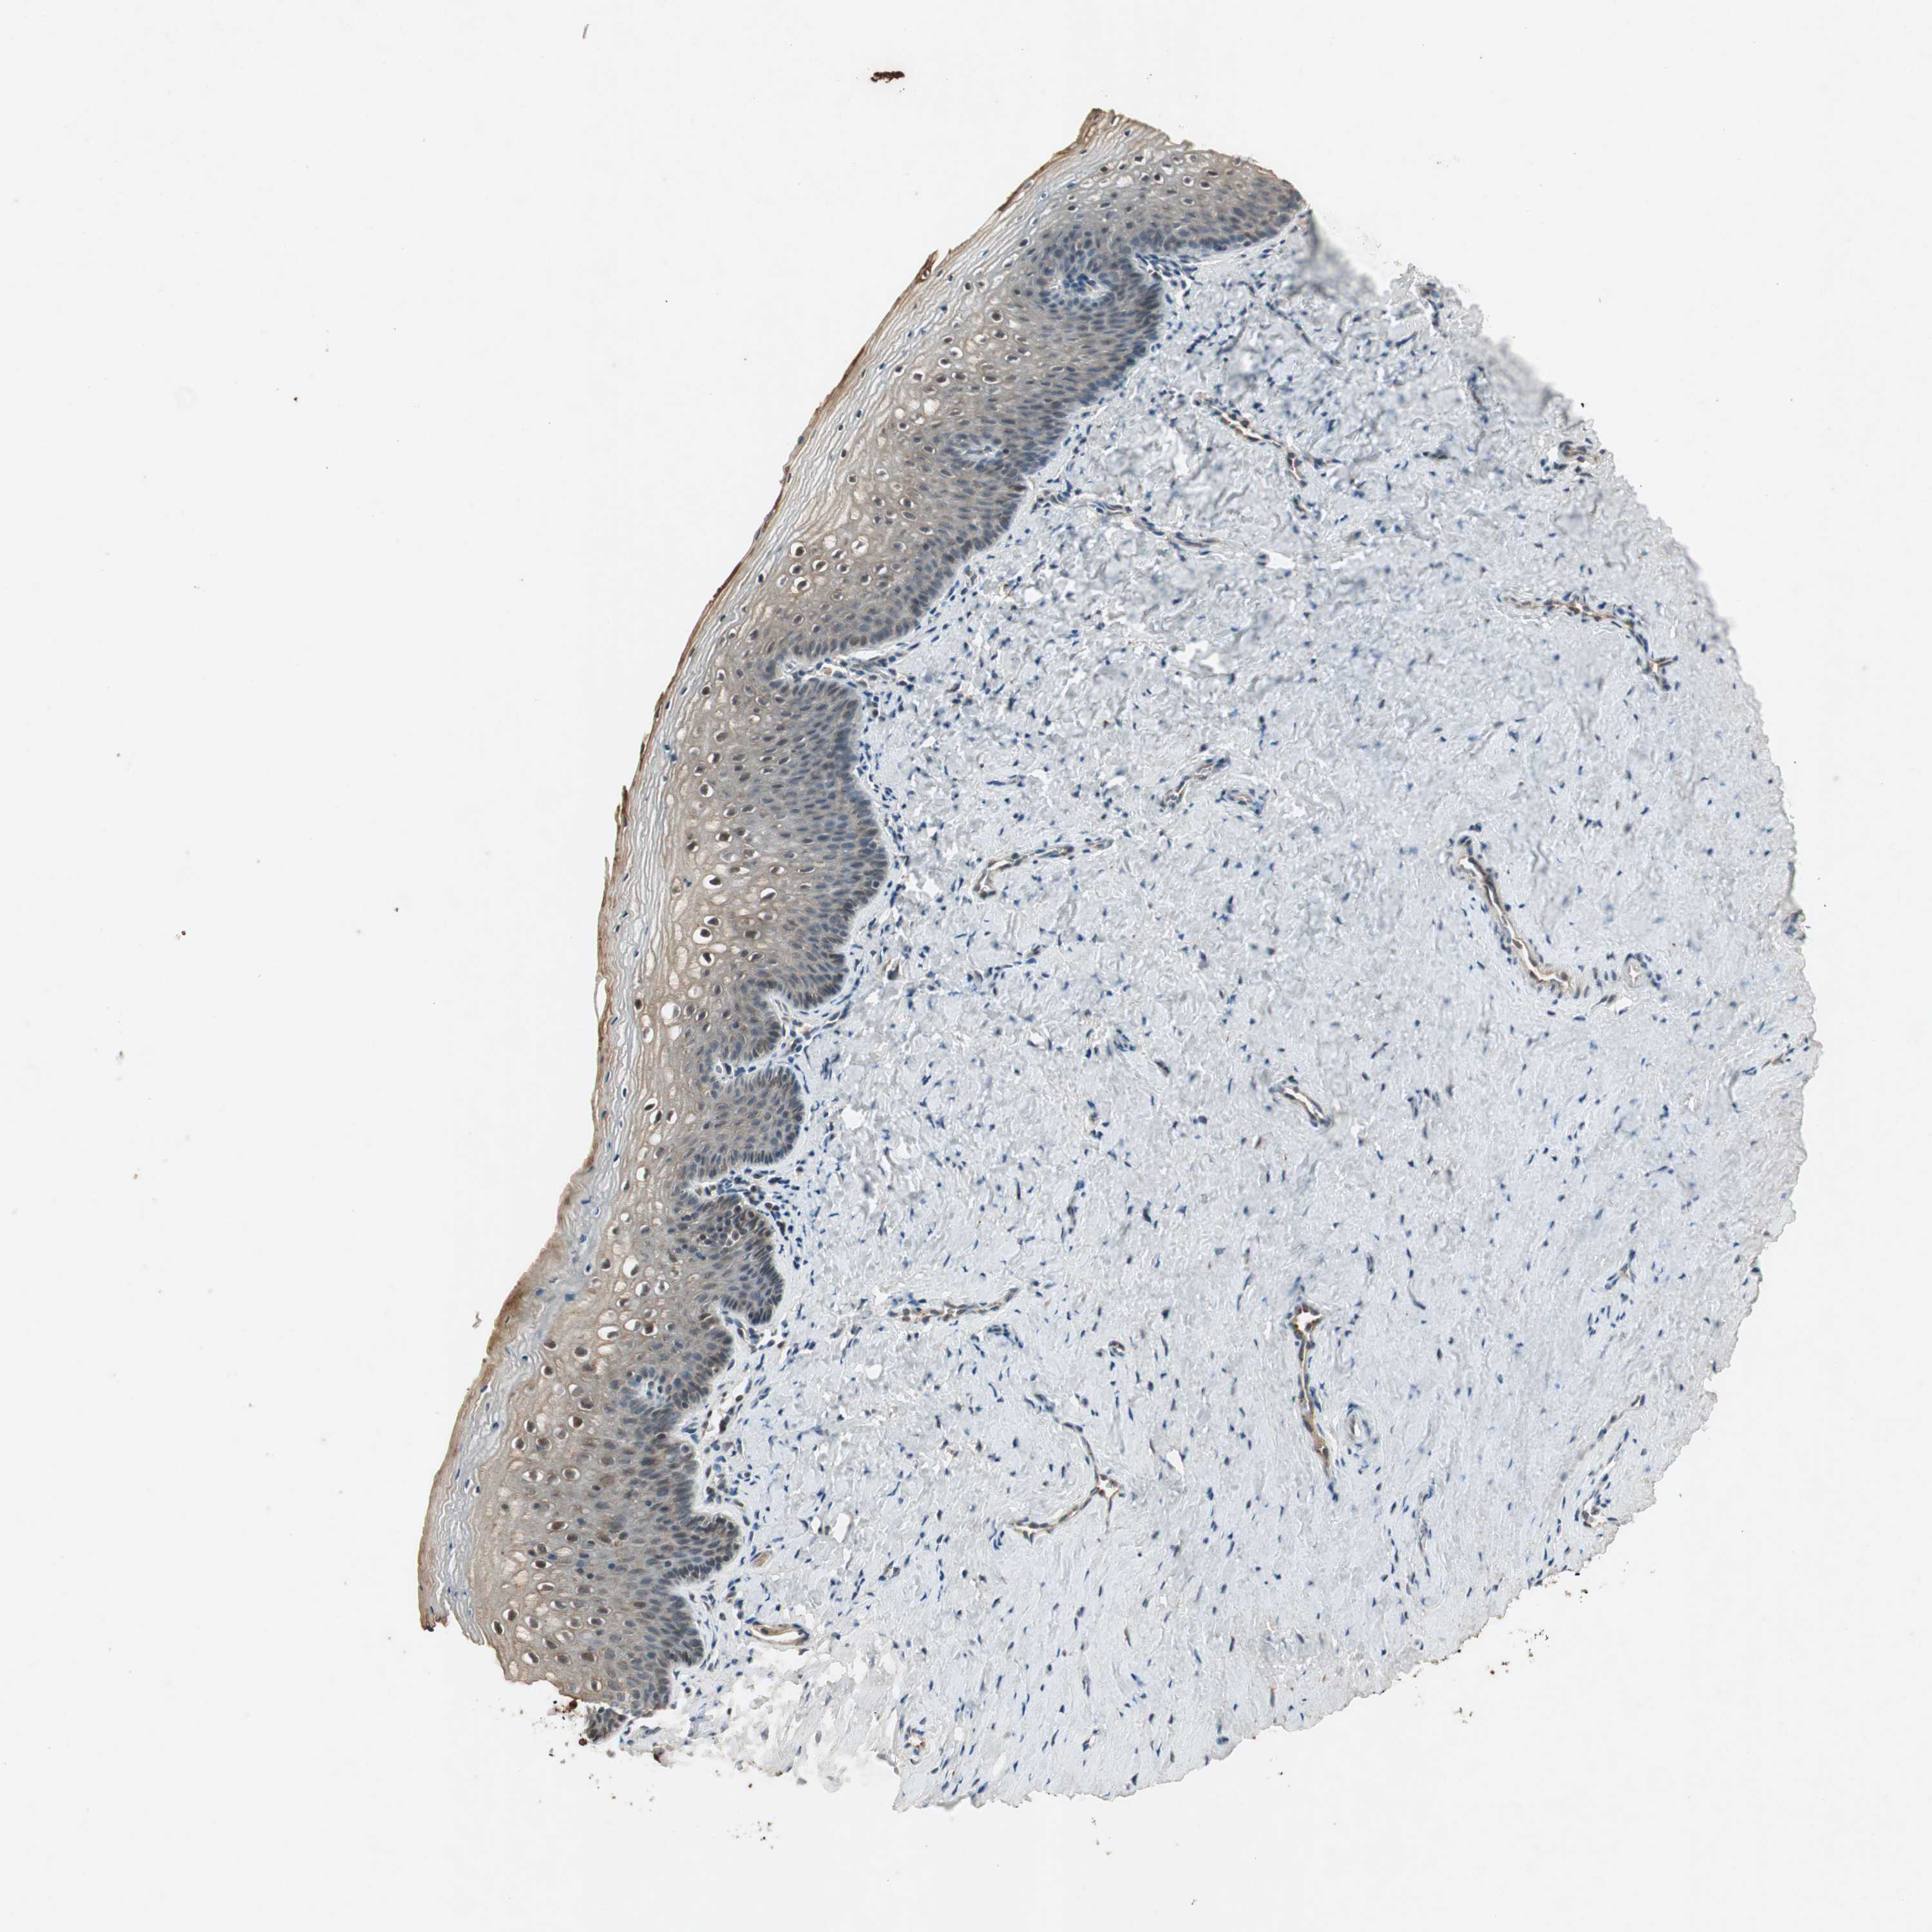

VAGINA - Antibody stainingi

Antibody staining in the annotated cell types in the current human tissue is reported as not detected, low, medium, or high, based on conventional immunohistochemistry profiling in selected tissues. This score is based on the combination of the staining intensity and fraction of stained cells.

Each image is clickable and will lead to virtual microscopy that enables deeper exploration of all samples and also displays staining intensity scores, fraction scores and subcellular localization as well as patient and tissue information for each sample.

Antibody HPA027804Antibody HPA027805Antibody HPA027806Antibody CAB009320

Squamous epithelial cells Not detectedNot detectedNot detectedLow